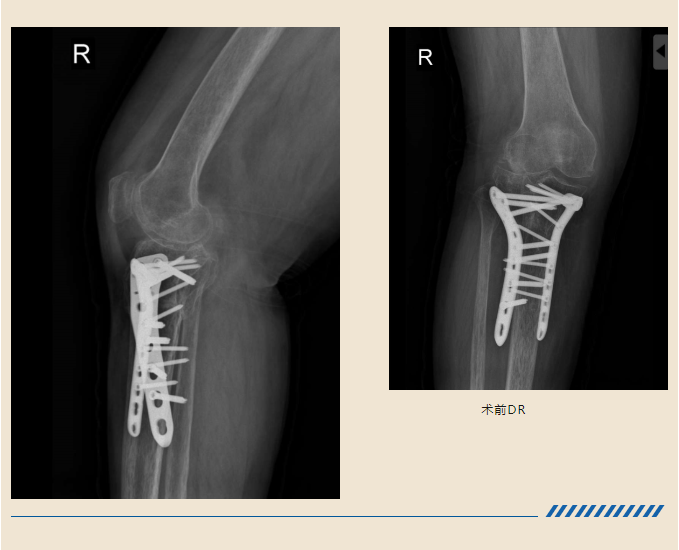

造成了右腿的胫骨平台骨折

在当地医院手术治疗后

结果却不尽人意

骨折部位畸形愈合

因为有很多骨缺损、技术难度

比如膝关节局部软组织

瘢痕松解困难

术中关节面显露困难